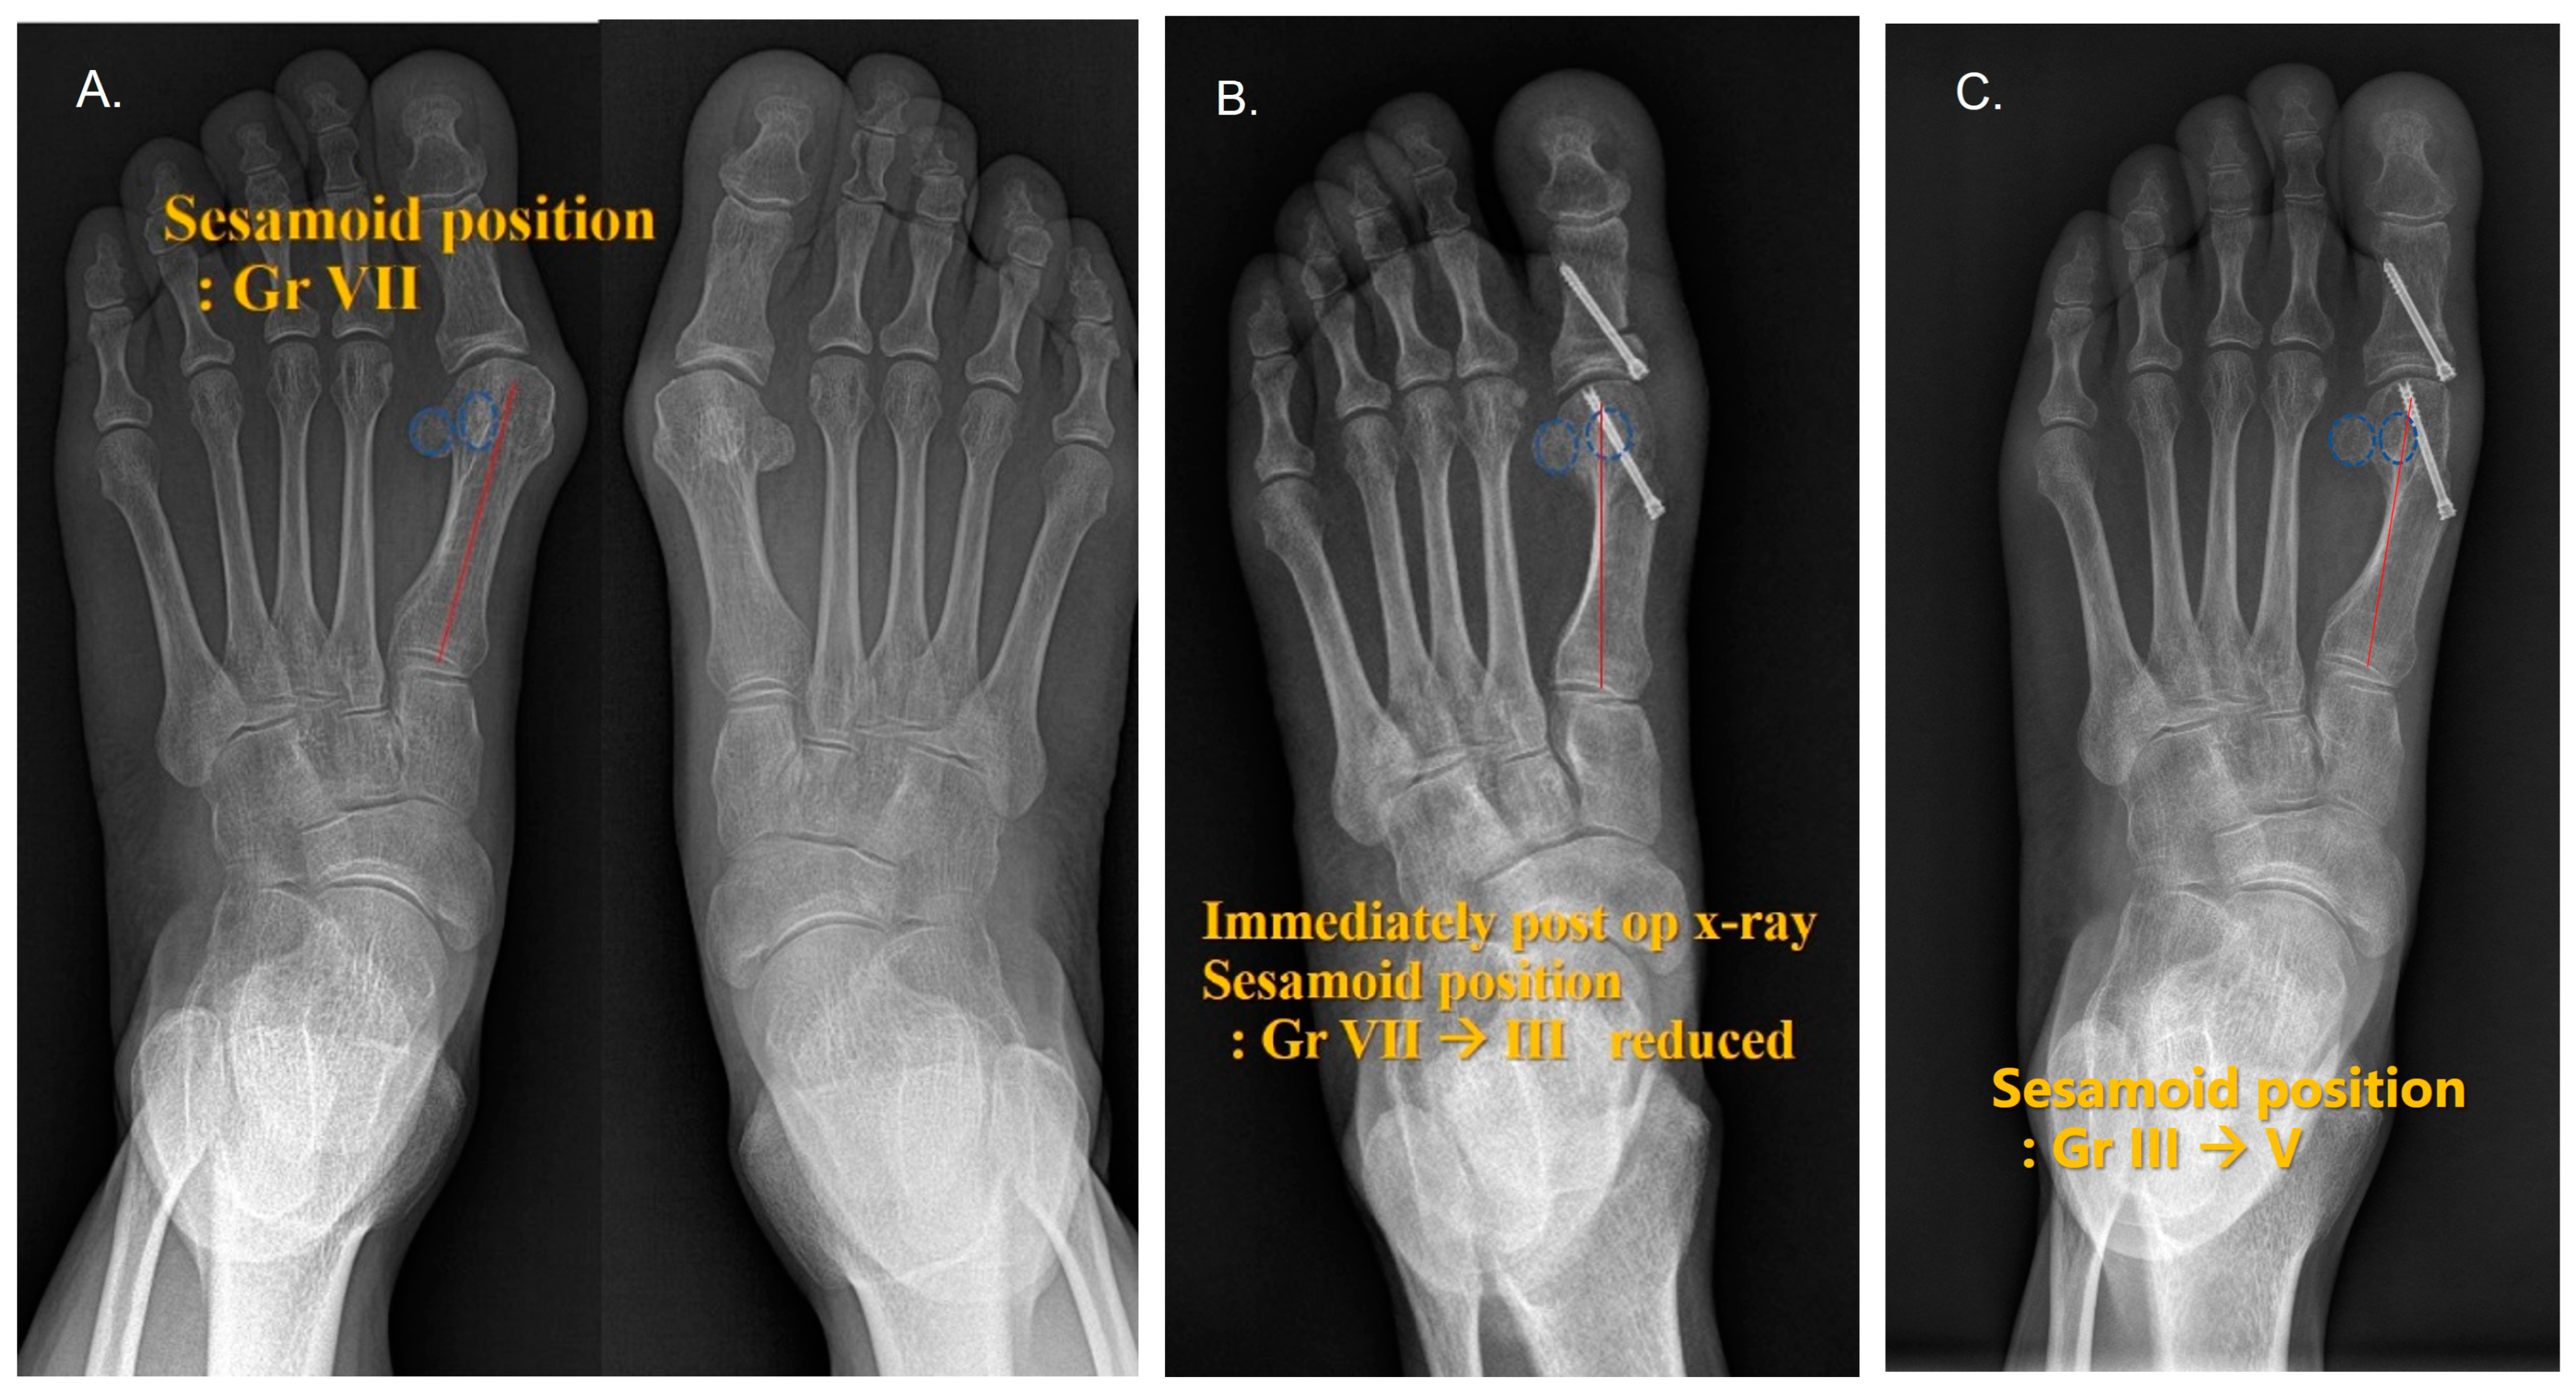

Sesamoid Bone X Ray Collection 2022 Sesamoid Bone X Ray Collection 2022

Sesamoid Bone X Ray

Sesamoid fracture | Radiology Reference Article | Radiopaedia.org Radiology Review - Sesamoid fracture | Axis Sports Med Toes (sesamoid view) | Radiology Reference Article | Radiopaedia.org Sesamoid | Radiology Reference Article | Radiopaedia.org Sesamoid bone - Wikipedia Sesamoid Bone X Ray